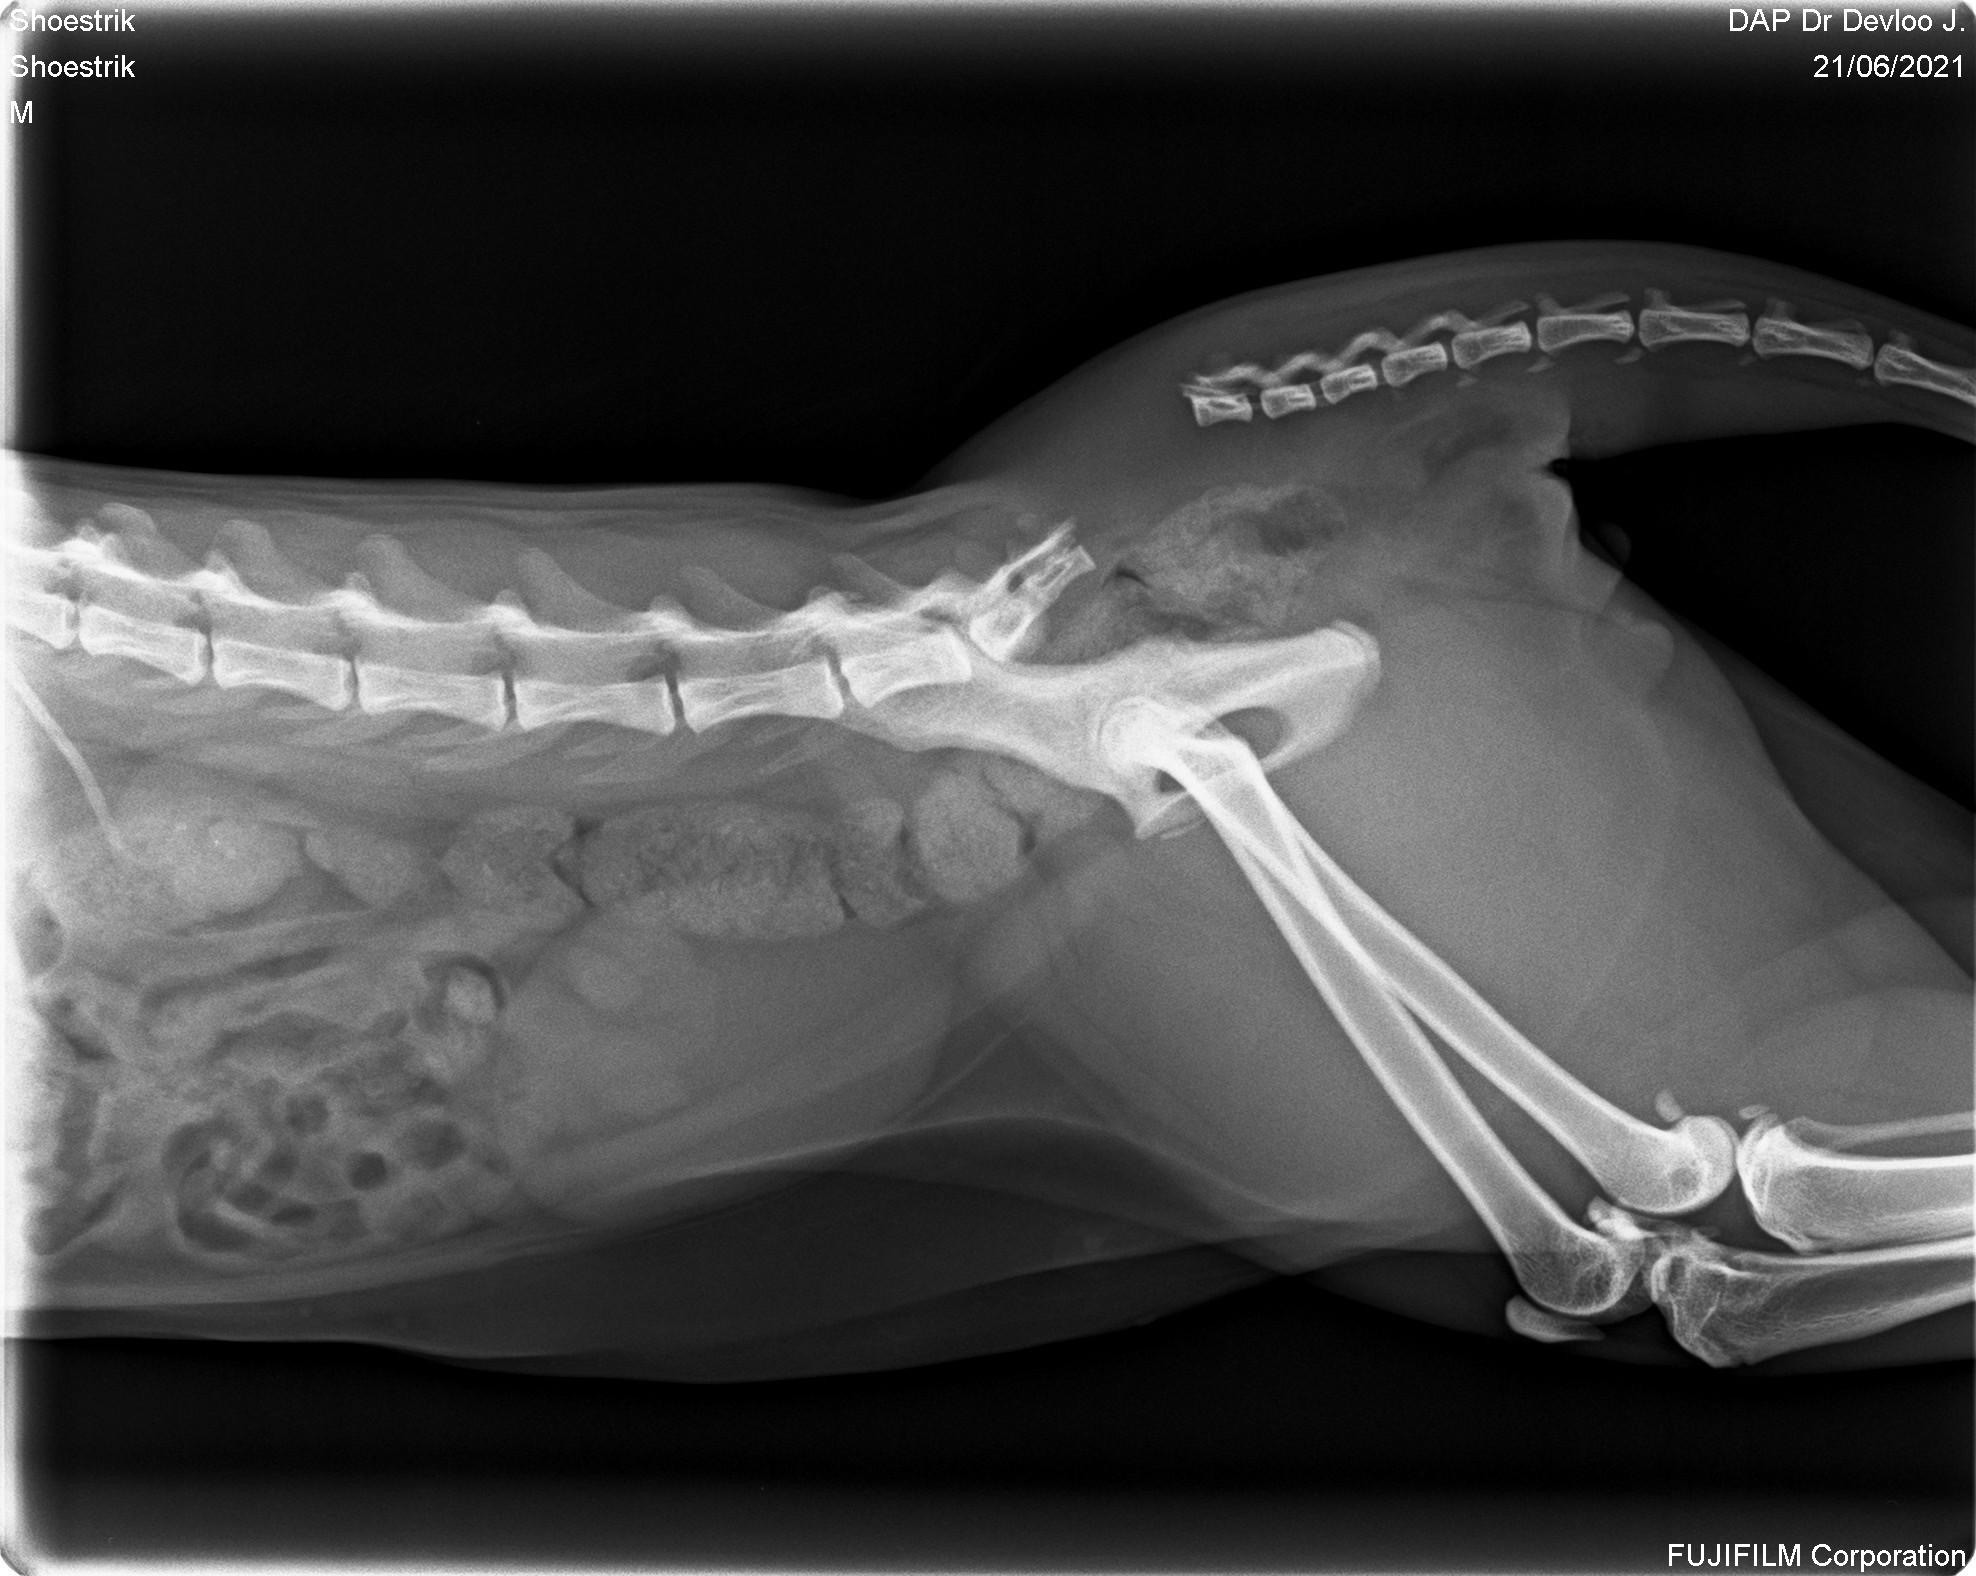

Никто не готовился к тому, что в два года его позвоночник будет сломан. Мы так и не узнали кто это сделал. Хвост был просто оторван, вряд ли он сам себя так повредил.

“Шансов три процента.” - вот что мы услышали в клинике.

Он пережил две операции. Прошёл тяжелую реабилитацию.